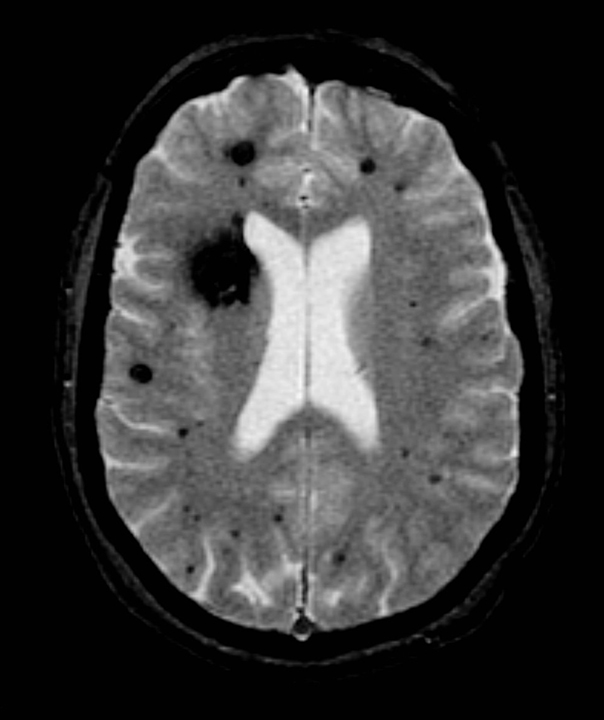

Brain cavernomas. Coronal cut MRI image of the brain ca Openi Cavernoma And Radiosurgery Conservative management with serial imaging and observation, microsurgical resection, and stereotactic radiosurgery are the 3 main options for the management of. Intracranial cavernous malformations (cms) are congenital vascular. Currently, the only available treatment options for ccms are surgery (resection, stereotactic radiosurgery) and management of. Radiosurgery in brain locations considered high risk for resection may be. Cavernoma And Radiosurgery.